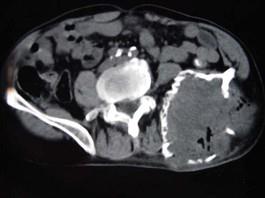

问题 患者,女性,68岁,近2年来感左髋部疼痛,活动后加重,2周前由于剧烈运动后左下肢活动不能,查体左髋部压痛明显,皮肤稍显红肿,请结合所提供的图像,选择最佳选项 ( )

选项 A、转移瘤 B、软骨肉瘤 C、骨巨细胞瘤 D、动脉瘤样骨囊肿 E、骨囊肿

答案 D